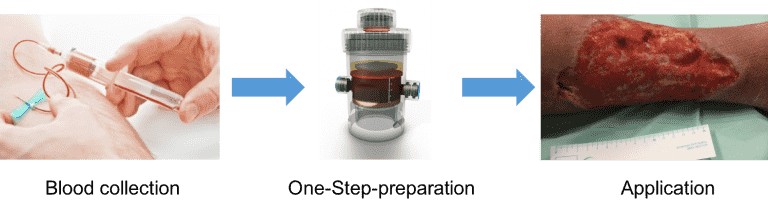

EmaCure®: Entwicklung eines personalisierten therapeutischen Ansatzes zur Wundheilung

Projektleiter: Dr. Philipp Moog

EmaCure® wird durch Konditionierung von peripheren Blutzellen unter wundsimulierenden physiologischen Bedingungen (Hypoxie, Temperatur) für einen definierten Zeitraum hergestellt. Dieser Ansatz stellt eine signifikante Verbesserung gegenüber den derzeit verfügbaren Systemen zur Herstellung von autologen, blutbasierten Zusammensetzungen, dar. Es ermöglicht eine Hypoxie induzierte Steigerung der Proteinkonzentration, im Vergleich zum Zeitpunkt der Blutentnahme.

EmaCure® kann in Form von Wundverbänden und injizierbaren Präparaten erfolgen, die vollständig zellfrei sind. Da die Proteinfaktoren aus dem autologen Blut des Patienten stammen, ist diese der therapeutische Ansatz patientenspezifisch. Unsere Forschungsbemühungen beschäftigen sich ebenfalls mit der Fähigkeit der generierten Sekretome auf unterschiedliche Gewebetypen.

Das EmaCure®-Konzept wird von einem multidisziplinären Forscherteam entwickelt, darunter Zellbiologen, Ingenieure, Kliniker und plastische Chirurgen sowie Spezialisten für translationale Therapien. Das Netzwerk der Kooperationsinstitute umfasst die TU München, die Hochschule München, die Fachhochschule München, sowie die Universitätsmedizin Göttingen.

Eine Patentanmeldung auf eines one-step device zur Vorbereitung und Bereitstellung der EmaCure®-Faktoren wurde erstmals im Februar 2012 eingereicht PCT/EP2013/051910;''Device based methods for localized delivery of cell-free carriers with stress-induced cellular factors''). Das Patent wurde im August 2013 veröffentlicht (IPN: WO 2013/113821 A1).